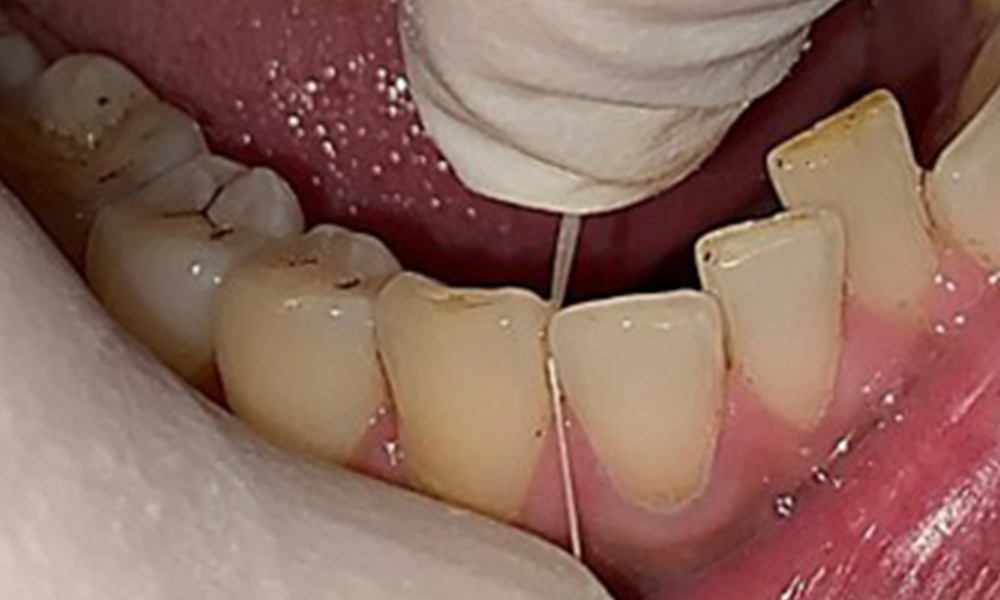

Close-up view of teeth

Fig. 5: Close-up view of teeth 45 to 47. The green arrows show dental attrition and erosions of the buccal cusps with partial enamel loss, © Dr R. Krapf

The patient has full dentition with a total of 28 teeth. There were noteworthy erosions and attritions. (Fig. 4, Fig. 5). Due to bruxism, the patient has been wearing a splint with an adjusted bite block at night for many years. The erosions were caused by long-term consumption of isotonic beverages. No periodontal bone loss or active caries were observed.